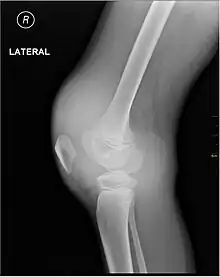

Lipohemarthrosis (blood and fat in the joint space) seen in a person with a subtle tibial plateau fracture. The arrow indicates a fluid level between the upper fat component and the lower blood component.

Synovial fluid analysis is another method to diagnose Hemarthrosis. It involves a small needle being inserted into the joint to draw the fluid.[6] Reddish-colored hue of the sample is an indication of the blood being present. Imaging tests are normally done. The tests also include MRI, ultrasound and X-ray test, which give better information about the joint inflammation.[7] Although MRI is superior method for this assessment, the US using the HEAD-US method performed by paediatric radiologists is a reliable tool for detection and quantification of haemophilic arthropathy in children in comparison to MRI.[8]